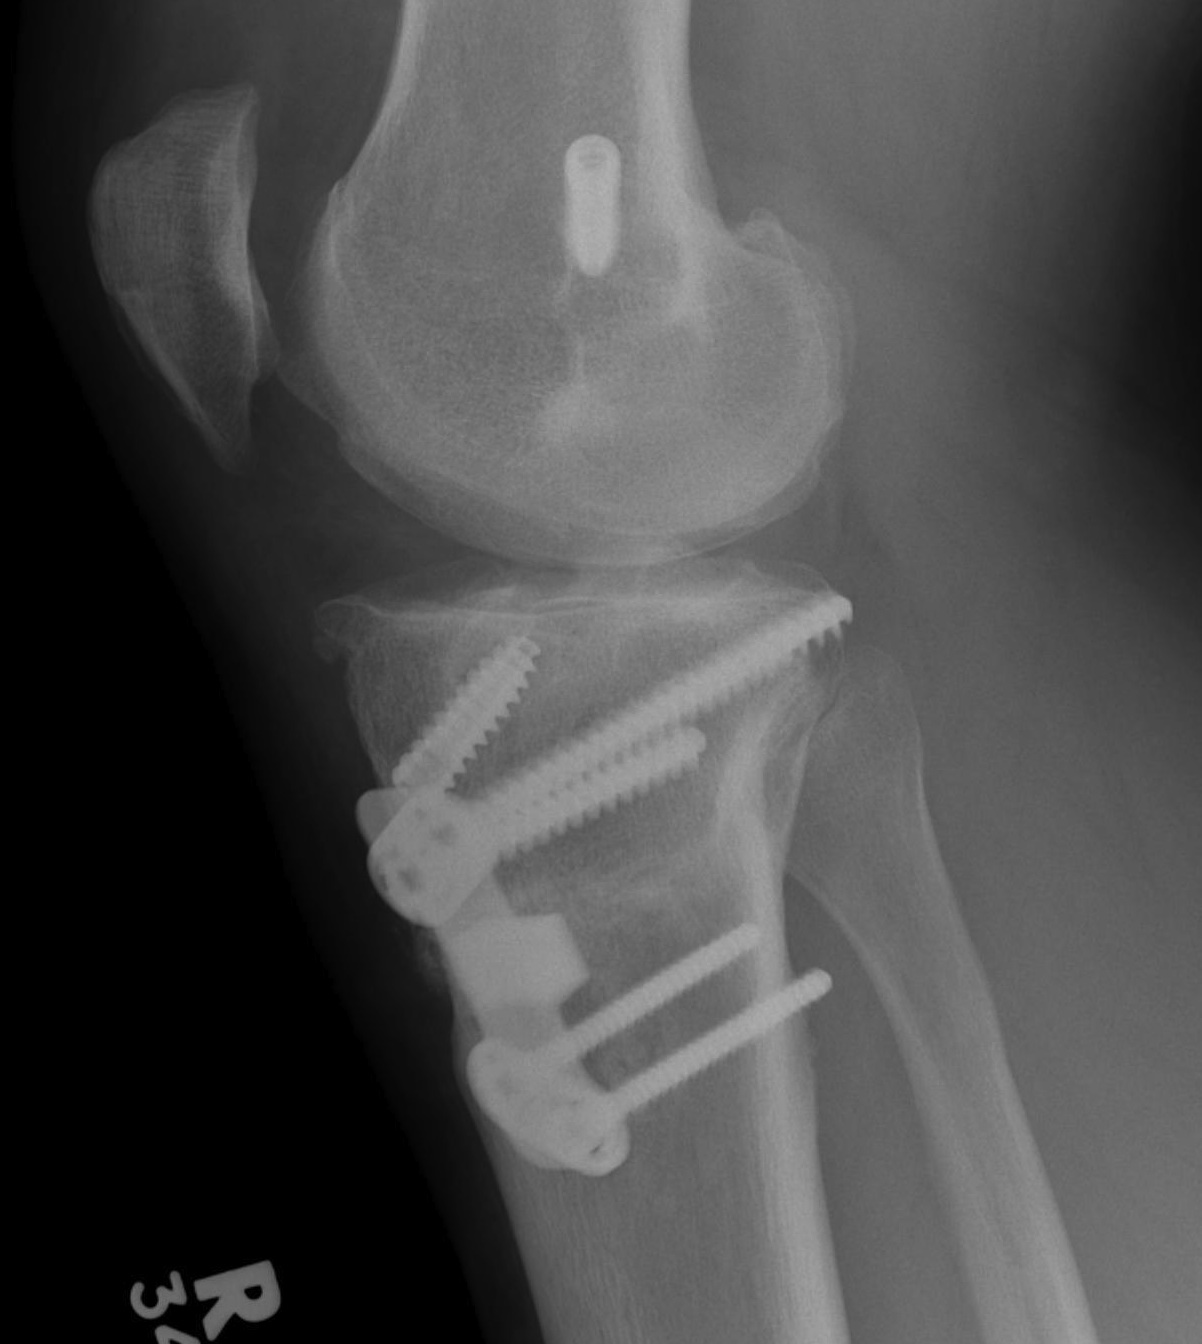

2. ACL + Medial Collateral

Epidemiology

Grade II MCL

- 75% chance ACL rupture

Indication for surgery

- MCL torn off tibia (usually off femur) and flipped up and over the pes anserinus

- won't heal in this position

- MRI all patients with MCL tenderness over tibal insertion

Patient with MCL and ACL instability

- reconstruct ACL

- reassess MCL at end of case

- if mildly unstable, advance / imbricate MCL on femoral side +/- tighten medial head gastrocnemius

- if severely unstable, reconstruct with hamstring or tendoachilles allograft